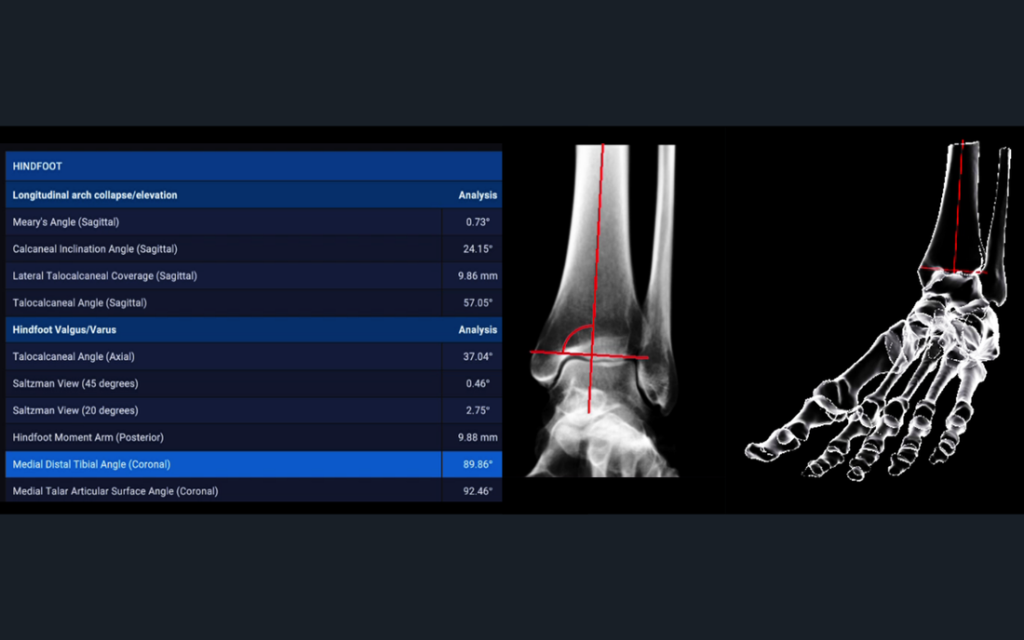

Automatic analysis of radiographic parameters, that support you in quantifying dislocations, deformities and suspected impingement

Excellent applicability for various diagnoses of the hindfoot and forefoot e.g., progressive collapse flat foot deformity and post-traumatic osteoarthritis